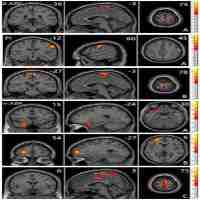

| Abstract | Objective: Clinically, it is very difficult to distinguish between major depressive disorder (MDD) and bipolar disorder (BD) in the period of depression. Increasing evidence shows that the insula is important in depression. We aimed to compare the resting-state functional connectivity (rsFC) of insular subregions in patients with MDD and BD in depressive episodes (BDD), who had never experienced manic or hypomanic episodes when they were scanned to identify biomarkers for the identification of two diseases. Method: We recruited 21 BDD patients, 40 MDD patients and 70 healthy controls (HC). Resting-state functional magnetic resonance imaging (rs-fMRI) was performed. BDD patients had never had manic or hypomanic episodes when they were scanned, and the diagnoses were determined by follow-up. We divided the insula into three parts including the ventral anterior insular cortex (v-AIN), dorsal anterior insular cortex (d-AIN) and posterior insula (PI). The insular-based rsFC was compared among the three groups, and an analysis of the correlation between the rsFC value and clinical scale was carried out. Results: BDD and MDD patients demonstrated decreased rsFC from the v-AIN to the left superior /middle frontal gyrus compared with the HC group. Versus MDD and HC groups, BDD patients exhibited decreased rsFC from the v-AIC to the area in the left orbital frontal gyrus and left superior temporal gyrus (included temporal pole), from the PI to the right lateral postcentral gyrus and from all three insular subregions to the somatosensory and motor cortex. Meanwhile, a correlation between the rsFC value of the PI-right lateral postcentral gyrus and anxiety score was observed in patients. Conclusion: BDD and MDD patients indicate similar decreases in insular connectivity in the dorsal lateral frontal regions, and BDD patients have specific decreased insular connectivity, especially in the somatosensory and motor cortex, which may be used as imaging evidence for clinical identification. |